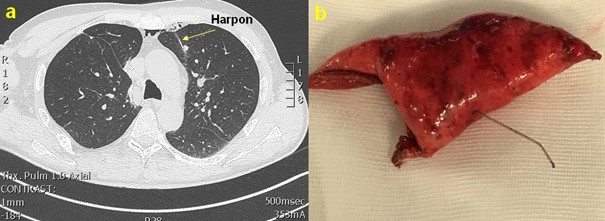

Figure 1. a. Repérage pré-opératoire d’un nodule profond lobaire supérieur gauche sous CT-Scan. b. Pièce opératoire après wedge résection.

Dans ce cas de figure, le patient quitte en moyenne l’hôpital au deuxième jour post-opératoire. Le repérage d’un nodule pulmonaire de petite taille ou situé en profondeur peut être périlleux en thoracoscopie puisque la palpation n’est pas possible ou difficile. Pour pallier à ce problème, le nodule peut être repéré par un harpon positionné en salle de radiologie sous CT-scanner immédiatement avant la procédure chirurgicale (figure 1).